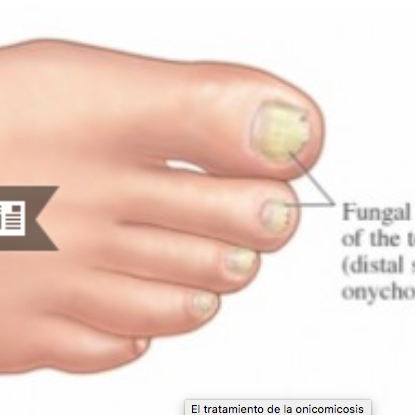

La podología (del griego podo, pie y logos, estudio) es una ciencia que tiene por objeto el estudio y el tratamiento de las enfermedades y alteraciones que afectan al pie, cuando dicho estudio no rebasa los límites de la cirugía menor.